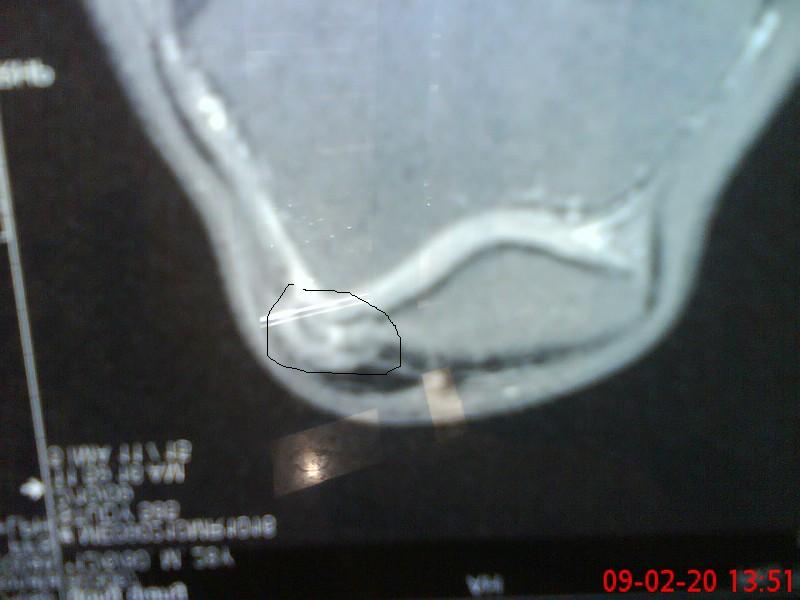

上三张片子,看看我的病根在那儿,圈起来那块是多出来的。。

做完手术的时候我问开刀的徐雁,他说是膑骨先骨折后增生。

我要是在受伤后养好再骑车,也许就不会增生了。是我磨了大半年慢慢增生出来的。